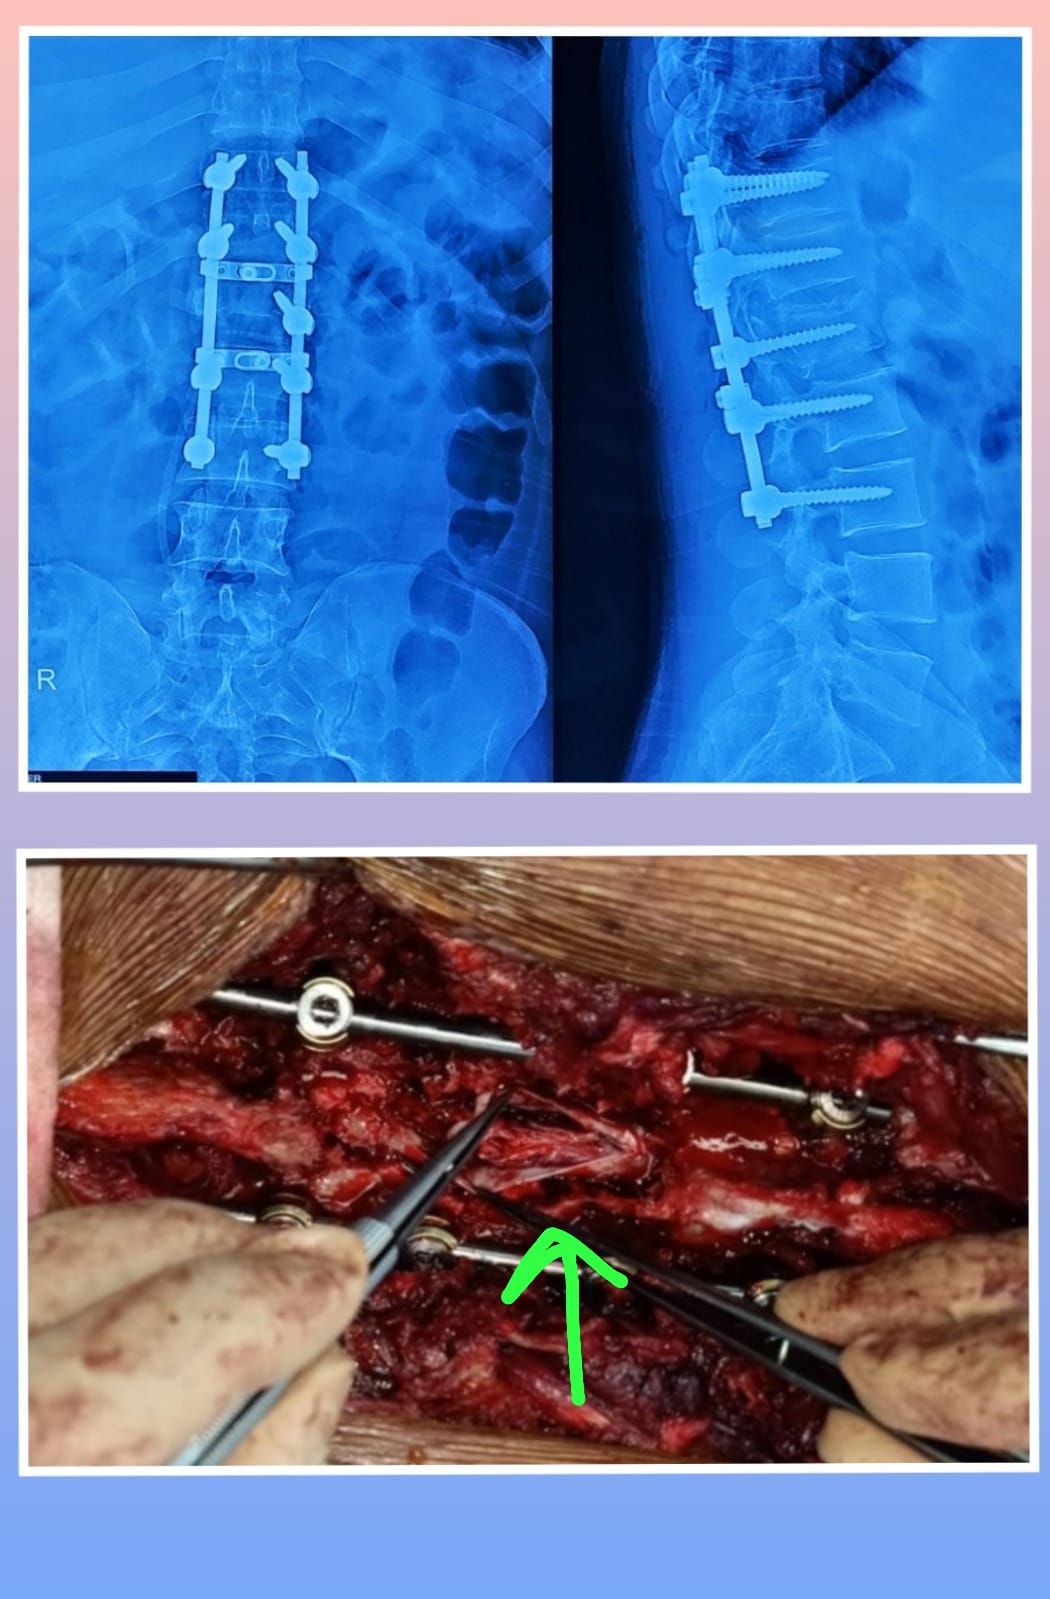

X-ray

Warning: Graphic Content

The following section contains graphic images of surgical procedures. These images are intended for educational purposes and may be disturbing to some viewers. Viewer discretion is advised.

Surgeries